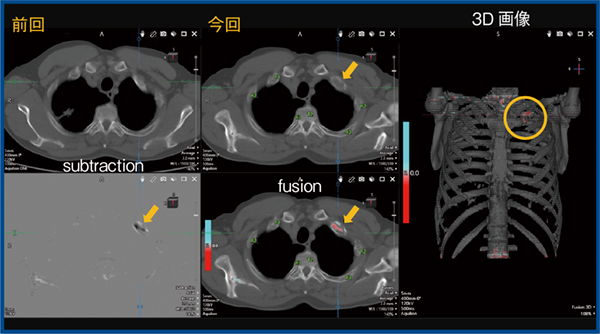

2.肺がん術後

図2は肺がん術後の症例で,前回画像と比較すると左第1肋骨に溶骨性変化(↓)が出現している。通常の2D画像による観察では,注意して観察しないと見逃す可能性がある病変であるが,TSBの3D画像では溶骨性変化の部分が赤く描出されており(図2 ○),見逃しを防ぐことができる。

図2 肺がん術後